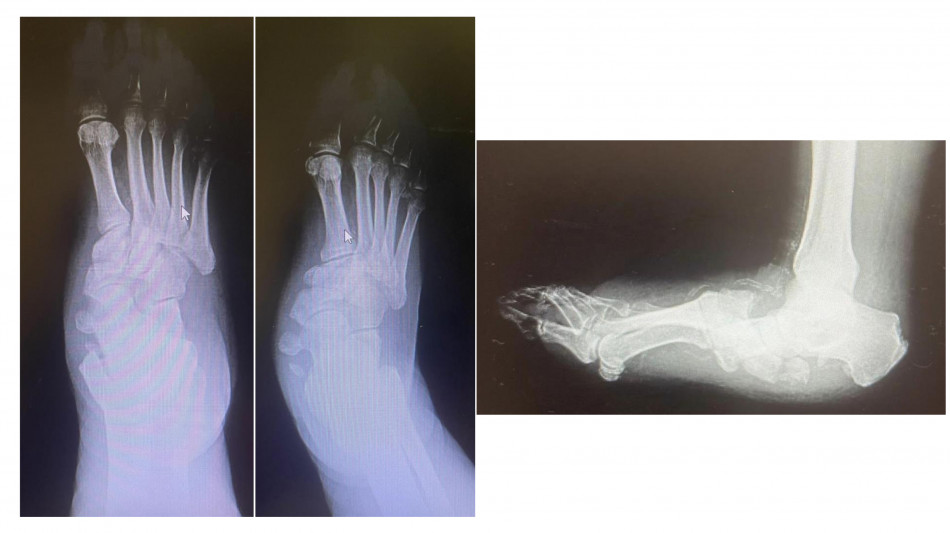

Diabete, al Gemelli soluzioni avanzate per il piede di Charcot

La rara complicanza che porta a deformità richiede complicati interventi ortopedici

Tra le molte complicanze del diabete c'è anche il cosiddetto piede di Charcot (neuro-osteoartropatia di Charcot), una patologia rara ma gravemente invalidante e alto rischio di amputazione se non diagnosticata in tempo. Il policlinico universitario Gemelli di Roma è una delle poche strutture italiane dove è possibile gestire da un punto di vista internistico e diabetologico ed effettuare i complicati interventi di salvataggio ortopedico di questi piedi deformati e disabilitati. Condizione predisponente del piede di Charcot è la neuropatia diabetica. A essere affetto da neuropatia è almeno il 30-40% delle persone con diabete; il piede di Charcot compare solo nello 0,05% dei casi. "Questi pazienti hanno una grave disregolazione dei processi infiammatori, anche a seguito di uno stimolo banale, come il sovraccarico sul piede - spiega Dario Pitocco, associato di endocrinologia all'Università Cattolica del Sacro Cuore e direttore della Uosa di diabetologia della Fondazione policlinico Gemelli Irccs -. Molto spesso sono colpite persone che passano molto tempo in piedi (camerieri, cuochi) o che utilizzano molto il piede come gli autisti. Il fatto che la neuropatia attutisca il dolore fa sì che la diagnosi sia tardiva". Se questa fase diagnostica viene mancata, la malattia progredisce rapidamente verso la fase cronica. "Assistiamo a una progressiva alterazione dei tessuti molli, delle articolazioni e delle ossa del piede - spiega Carlo Perisano, ricercatore in ortopedia e traumatologia all'Università Cattolica del Sacro Cuore Campus e dirigente medico presso la Uoc di ortopedia e traumatologia del Gemelli -. Il piede si deforma fino a diventare un 'piede a dondolo', a causa della mal consolidazione dell'osso". Queste, in stadio avanzato, possono essere corrette solo da un complesso intervento, che di fatto diventa una chirurgia di salvataggio dell'arto. "Sono interventi che mirano a correggere deformità estremamente complesse del piede e della caviglia e che prevedono una serie di procedure chirurgiche (nell'ambito dello stesso intervento), quali osteotomie correttive e successive osteosintesi - prosegue Perisano - . Questo consente la ricostruzione di un asse del piede e della caviglia, per permettere al paziente di tornare a camminare".